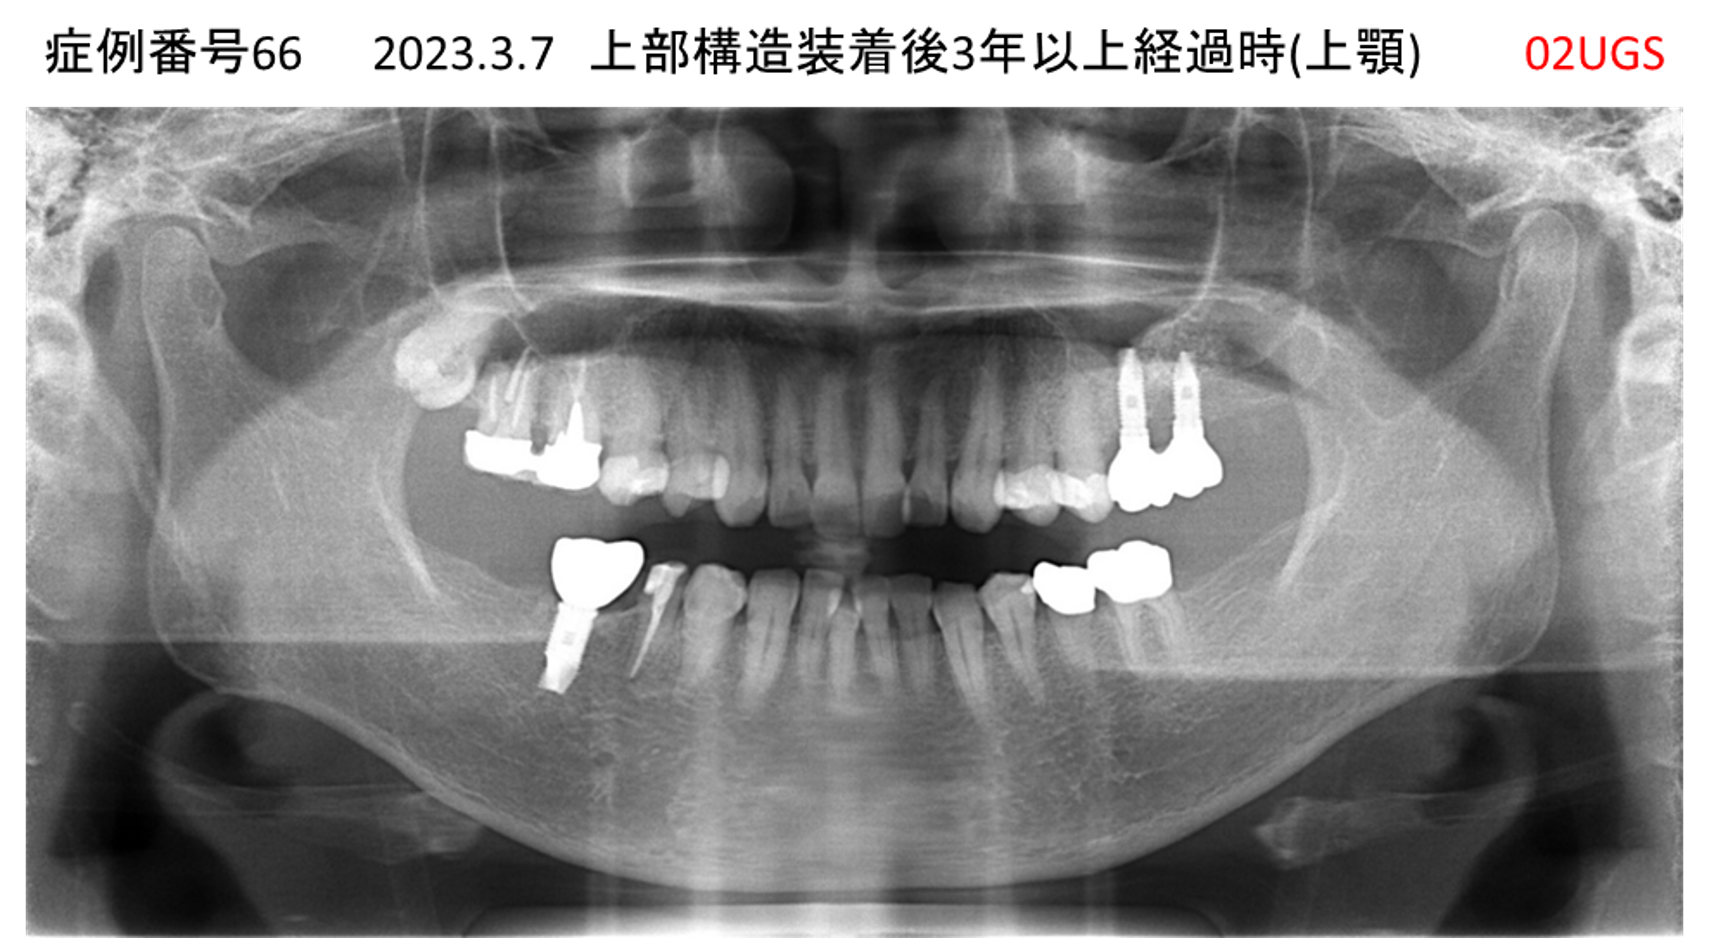

かめない/上の歯が揺れてきた患者様のインプラント症例

| 治療名称 |

インプラント |

| 治療費用 |

390万円+税 |

| 治療期間 |

6か月 |

| 患者さんの症状(主訴) |

かめない。上の歯が揺れてきた。 |

| 治療内容 |

サイナスリフト、抜歯即時インプラント |

| 治療結果 |

上の歯の揺れが収まった。噛めるようになった。食事がおいしい。 |

| 治療の注意点(リスク/副作用) |

インプラントが壊れたら再治療が必要 |